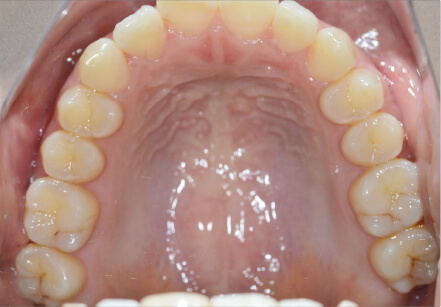

9歳

/

男性

相談内容

下の歯が重なっている。

カウンセリング・診断結果

myoからの移行

治療内容・方法

全額アライナー矯正

術後の経過・現在の様子

上下3〜3fix使用

治療のリスク

痛み・歯根吸収・歯肉退縮・虫歯・後戻り

費用・治療期間

880,000円、1年2ヶ月